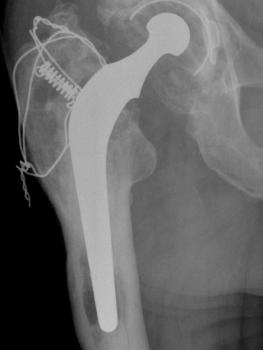

Stem insertion: never use the winged centralisers with any 35.5 or 37.5  No 1 or 2 offset stems – they may jam distally preventing component insertion. Use the simple wingless design or alternatively, snap off two wings and keep the 3rd in place, but put on the lateral side of the stem to encourage away from the lateral side of the femoral canal (Figure 3, Figure 4, Figure 5).

(Figure 6): Insertion by hand (with cement pressurisation): avoids impingement of the insertion device and also wobbling the stem as the device is dis-engaged. A small amount of cement over the lateral shoulder will prevent the stem dissociating from the mantle in the event of a dislocation being manipulated back into joint.